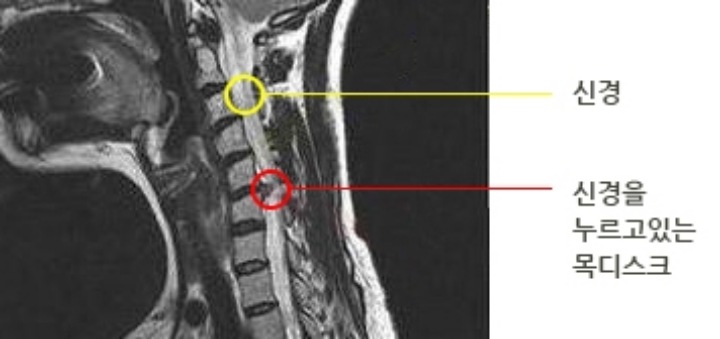

세 번째는 수술적 치료입니다. 목 디스크 증상이 심할 경우 결국 수술을 하셔야 하는데요. 수술은 경추 전방 고정술, 인공 경추 추간판 전치환술 등이 있으며 목의 신경을 누르고 있는곳을 수술을 통해 치료를 하는 방법입니다.